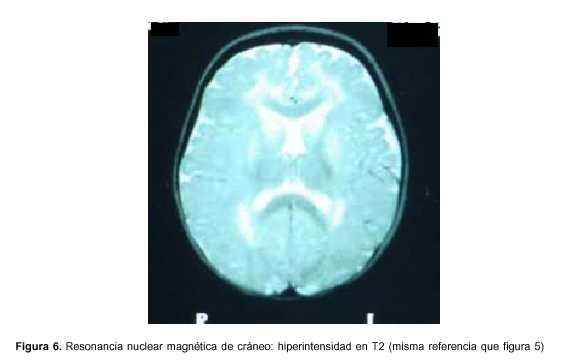

Exámenes paraclínicos realizados: hemograma: hemoglobina 9,8 g%, glóbulos blancos 11.900 elementos/mm3, plaquetas 377.000 elementos/mm3, azoemia 0,80 g/l, creatininemia 0,39 mg/dl, ionograma: Na 141mEq/l, K 4,3 mEq/l, Ca 1,2 mmol/l, glicemia 0,69 g/l, gasometría venosa: pH 7,36, exceso de base –6, HCO3 18,2 mEq/l, funcional y enzimograma hepático: bilirrubina total 0,24 mg/dl, bilirrubina directa 0,03 mg/dl, bilirrubina indirecta 0,21 mg/dl, transaminasas glutámico oxalacéticas (TGO) 123 U/l, transaminasas glutámico pirúvica (TGP) 101U/l, gamaglutamiltranspeptidasa 28 U/l, fosfatasa alcalina 479, lactato deshidrogenasa (LDH) 601, colinesterasa 9.183; examen de orina: límpida, vogel 2, ácida, densidad 1020, sin elementos anormales, líquido cefalorraquídeo (LCR): citoquímico incoloro, glucosa 0,54 g/l, proteínas 0,32, 10 elementos/mm3, a predominio mononucleares, estudio bacteriológico del LCR estéril, reacción en cadena de polimerasa en LCR para grupo herpes virus tipo 1 y 2 negativo, inmunoelectroforesis de LCR normal. Ácido láctico de LCR normal, HIV negativo, VDRL negativo, electroencefalograma (EEG): sufrimiento cerebral difuso sin actividad epileptógena focal, tomografía axial computarizada (TAC) de cráneo: normal, resonancia nuclear magnética (RNM) de cráneo: hiperintensidad en T2 a nivel de sustancia blanca subcortical, periventricular, núcleos lenticulares y pedúnculos bilateral y simétrica (figuras 5 y 6), ácidos orgánicos urinarios: aumento del ácido 3-hidroxiglutárico y ácido glutárico, carnitina plasmática: total: 32 mmol/l (valor normal 46-70); libre: 25 mmol/l (valor normal 41-58); libre %: 78 (valor normal 80%-90%).

Tanto los pacientes sintomáticos como los presintomáticos y aquellos con macrocefalia habitualmente tienen características neuroimagenológicas particulares: dilatación de la cisterna insular, regresión de los lóbulos temporales e hipodensidad de los núcleos lenticulares(19); puede verse también aumento de LCR a nivel de los lóbulos temporales y frontales así como compromiso de la sustancia blanca(3,19,20). Este aumento puede facilitar el sangrado de los vasos que atraviesan la zona ante un mínimo traumatismo, determinando sangrado subdural crónico y hematoma a veces acompañado de hemorragia retiniana. Estos hechos han llevado al diagnóstico de maltrato infantil en algunos casos(6). Nuestra paciente presenta compromiso de sustancia blanca y de los núcleos lenticulares bilaterales, coherente con los hechos clínicos.